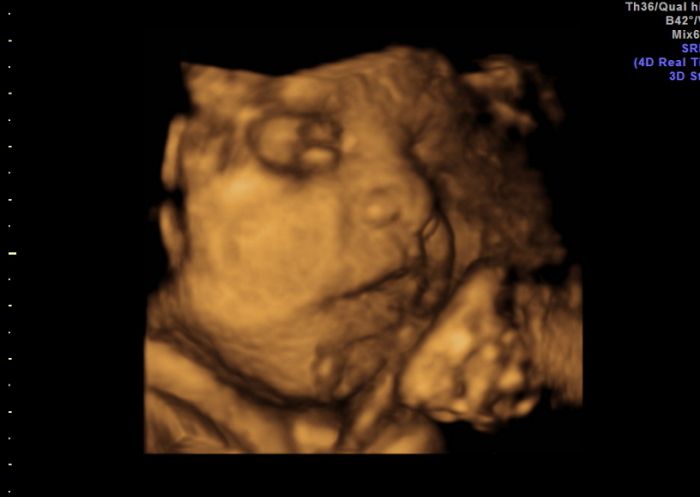

Já je přikládám

pindíka našeho

a na druhé a třetí fotce má před pusinkou pupečník, ale usmíval se na nás šmudlík malej náš